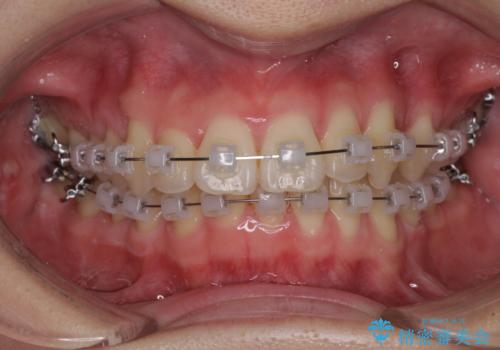

- 矯正装置

- クリアブラケット

ぱっと見はインビザラインによる矯正治療も可能と思われましたが、歯根が最も長い犬歯がクロスバイトになっており、インビザラインでは対応困難と判断され、ワイヤー装置にて矯正治療を行うこととしました。

クロスバイトになっている犬歯は、歯の移動に伴い装置を張り替えていくことで対応することとしました。

クロスバイト改善中には歯髄壊死を起こすリスクがあるため、神経に問題がないか確認しながら治療を進めて行く必要があります。